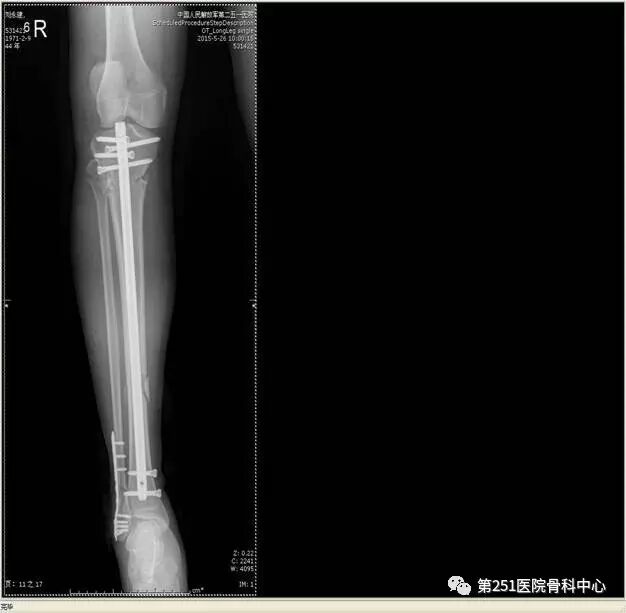

病例2:男性,44岁,车祸伤,双侧胫腓骨骨折(左侧)。

![]()